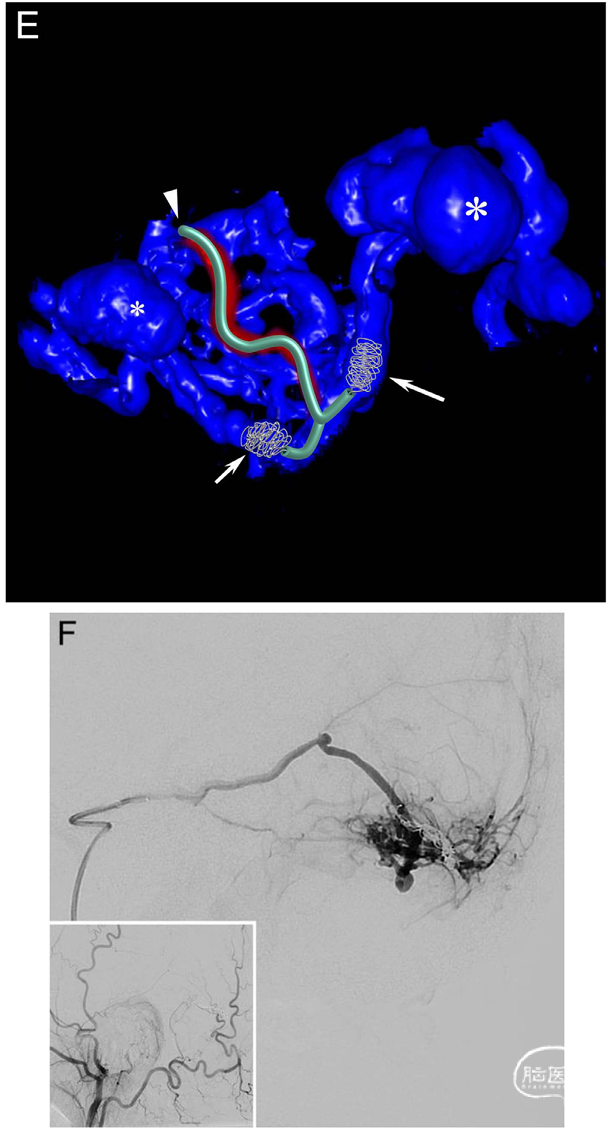

Fig. 2. A 60-year-old man (patient no. 2) presented with left-sided hemianopsia and headache due to an intracerebral hemorrhage in the right occipital lobe. A diagnostic DSA showed a high-grade tentorial DAVF (Borden type III, Cognard type IV). A. Right ECA injection in AP view shows the DAVF supplied mainly by an enlarged middle meningeal artery with arteriovenous shunting to medial (long arrow) and lateral (short arrow) venous drainage routes carrying several ectasias (medial: large asterisk, lateral: small asterisk). Insert: Right ECA injection in lateral view. B. Middle meningeal artery injection in lateral view shows that the main feeder (curved arrow) splits up into smaller pedicles before reaching the venous compartments. The medial venous ectasia (large asterisk) is located above the tentorium, while the lateral venous ectasia (small asterisk) is superimposed by the AV shunt. C. Lateral view of a superselective injection with the microcatheter tip (arrowhead) located distally in the main middle meningeal artery pedicle before entering the venous side. Both the medial (long arrow) and lateral (short arrows) venous drainage routes are visible with their medially (large asterisk) and laterally (small asterisk) located venous ectasias. D. Roadmap in lateral view shows that the 1.3F Headway™ Duo microcatheter (curved arrow) was navigated through the distal pedicle into the lateral draining vein (small arrows) first, where coils (double arrowhead) were deployed. After a minimal pullback and navigation into the opposite direction, coils were also deployed in the medial draining vein. Small asterisk: Venous ectasia on the lateral venous drainage route. E. Volume rendering technique (VRT) reconstruction based on a distal middle meningeal artery injection before coil deployment shows the pedicle (arrowhead) entering the initial venous segment, which divides into medial (long arrow) and lateral (short arrow) draining veins. The course of the microcatheter and the location of the coils are shown. Both the medial (large asterisk) and lateral (small asterisk) venous ectasias are visible. F. Control run in lateral view shows complete blockage of the arteriovenous shunting at the end of the procedure. Insert: Right ECA injection in lateral view shows stable occlusion of the DAVF after 3 months.